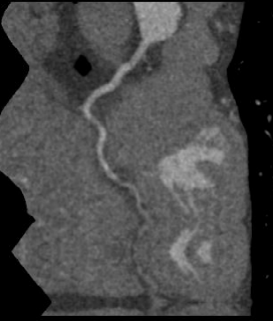

回旋支近端软斑块并管腔轻度狭窄